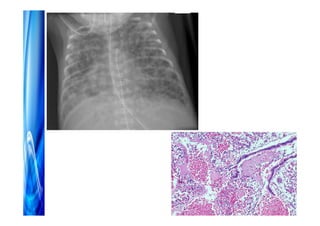

Distúrbios respiratórios

• Imaturidade estrutural (alveolalização > 32 S)

• Deficiência quantitativa e qualitativa de

surfactante

• Instabilidade da caixa torácica

• Baixa reserva muscular e ausência do reflexo

de engasgo

• Imaturidade e fragilidade dos capilares

pulmonares

• Superficie para trocas gasosas inadequada